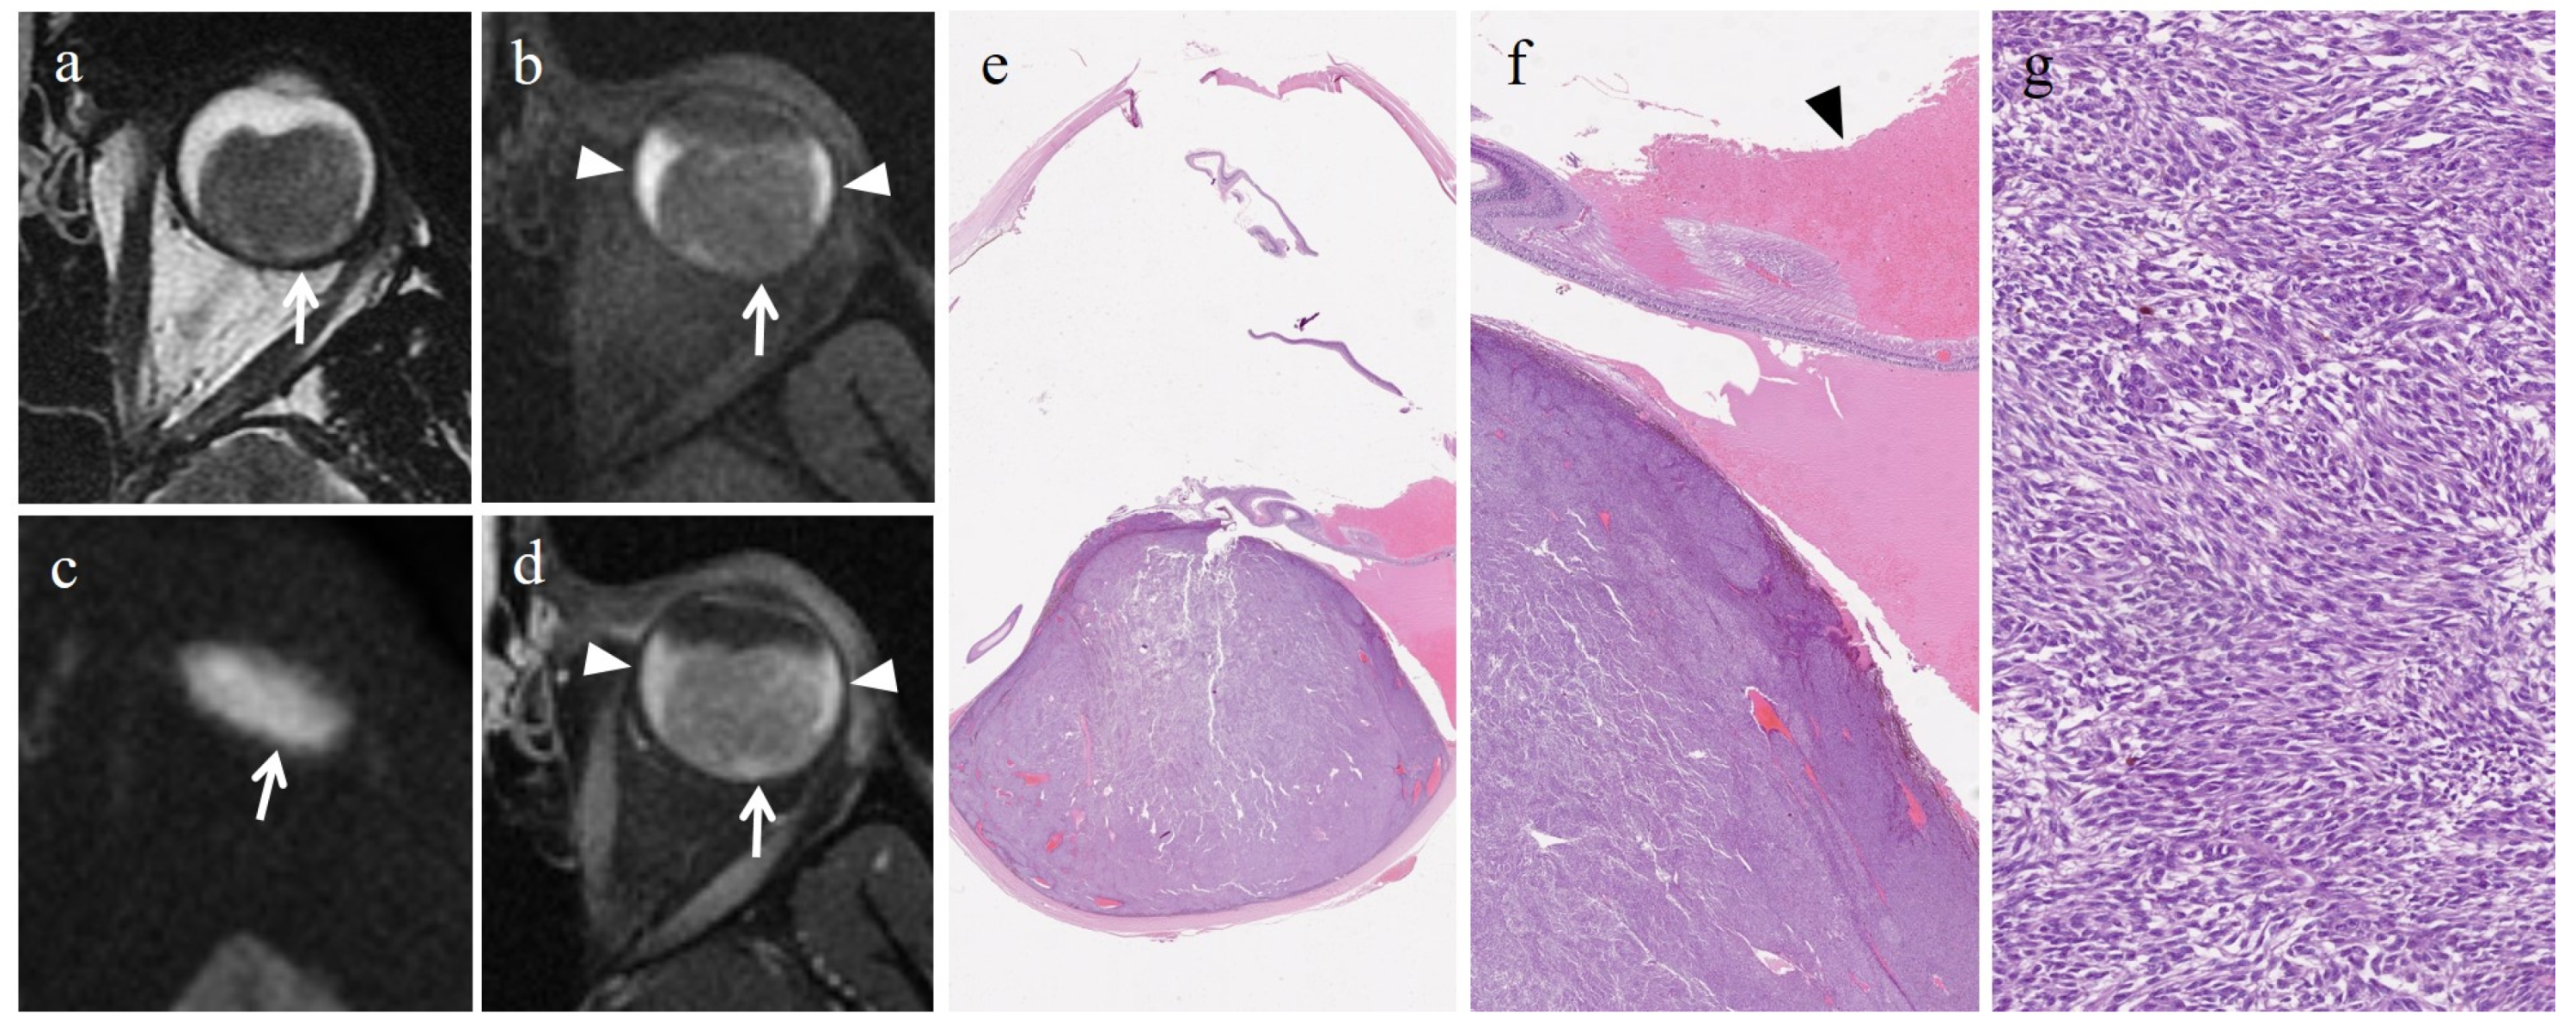

- Foti, P.V.; Inì, C.; Broggi, G.; Farina, R.; Palmucci, S.; Spatola, C.; Liardo, R.L.E.; Milazzotto, R.; Raffaele, L.; Salamone, V.; et al. Histopathologic and MR Imaging Appearance of Spontaneous and Radiation-Induced Necrosis in Uveal Melanomas: Initial Results. Cancers 2022, 14, 215. [Google Scholar] [CrossRef]